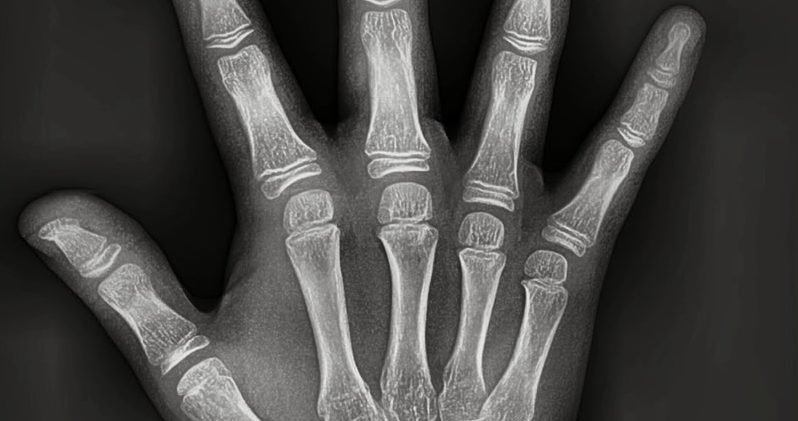

La radiografía Carpal o de la mano es el método de diagnóstico más usado y aceptado para determinar el nivel de maduración ósea de un individuo. Los patrones de osificación esqueletal ya establecidos científicamente, se utilizan para establecer la edad ósea.